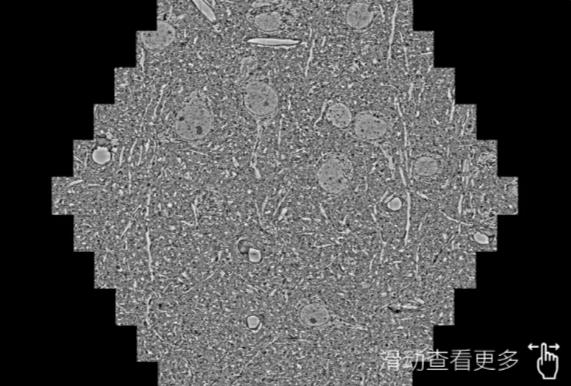

鼠脑切片。左图使用唐山蔡司唐山扫描电镜MultiSEM706对165μmx143pm面积区域成像,耗时仅需1.5秒。右图为鼠脑切片中30μm区域放大效果。样品由芝加哥大学B.Kasthuri提供。

使用蔡司高速唐山扫描电镜MultiSEM对1mm²人脑皮层组织进行高分辨成像,并对其中的各种细胞结构进行三维重构分析。左图展示了2x3mm²组织平面中锥体神经元的三维重构效果。右图显示了局部体积神经元三维重构。图像由哈佛大学chtman实验室提供,渲染图由D. Berger 制作。